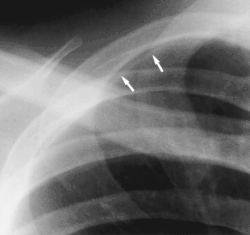

- Clavicular companion shadow is a thin soft-tissue stripe along the upper edge of the clavicle.[1]

- Rib companion shadows parallel the ribs and measure 1–5 mm in diameter project adjacent to the inferior and inferolateral margins of the first and second ribs and the axillary portions of the lower ribs. These companion shadows of the first and second ribs occur in 35% and 31% of the population, respectively. Rib companion shadows represent the fat and muscles in the intercostal space. The shadows that accompany the ribs may mimic pleural and lung disease.[2]

- Scapular companion shadow overlie the scapula, with a smooth, well-defined margin parallel to the medial border of the scapula. The companion shadow results from unusual radiographic position of the scapula, which causes a soft-tissue fold to occur along its medial border. Winging of the scapula may also be responsible for the shadow. Scapular companion shadows may be mistaken for a soft-tissue or pleural lesion.[3]